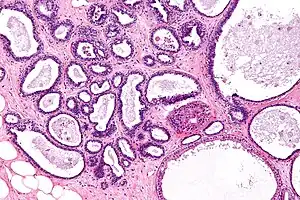

Micrograph showing fibrocystic breast changes. H&E stain.

Fibrocystic breast changes is a condition of the breasts where there may be pain, breast cysts, and breast masses.[1] The breasts may be described as "lumpy" or "doughy".[3] Symptoms may worsen during certain parts of the menstrual cycle.[1] It is not associated with cancer.[2]

Risk factors include an early age at first menstrual period and either having children late or not having children.[2] It is not a disease but represents normal breast changes.[3] Diagnosis typically involves ruling out breast cancer.[1] Fibrocystic change includes fibroadenomas, fibrosis, and papillomas of the breast.[1]